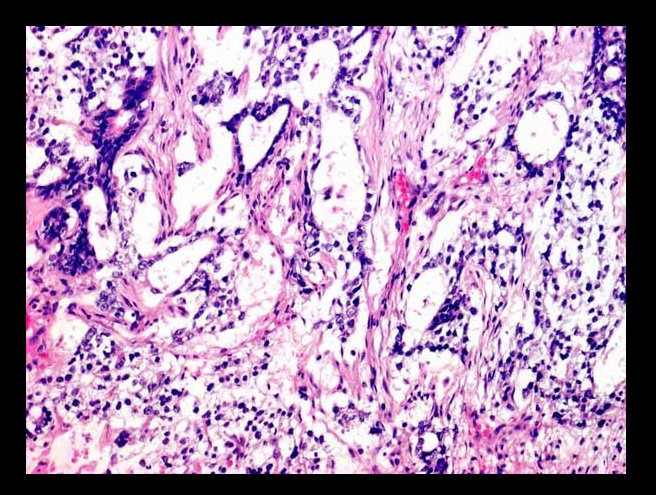

_Histology reveal cells with scanty cytoplasm and angulated, coffee-bean, grooved nuclei. The classic features are Call-Exner bodies., which are granulosa cells arranged in small follicles filled with eosinophilic secretions in the center.

Granulosa cell tumor: showing diffuse proliferation of small round cells.

Call-Exner Bodies seen in granulosa cell tumor